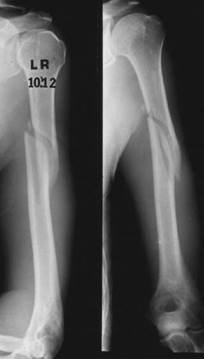

What do you see in these two radiographs?

T here is an AP view of the lower left leg showing multifragmented mid-shaft fractures of the tibia and fi bula, probably resulting from a high-energy impact. The chest radiograph suggests that there has been a signifi cant insult to the chest/lungs.